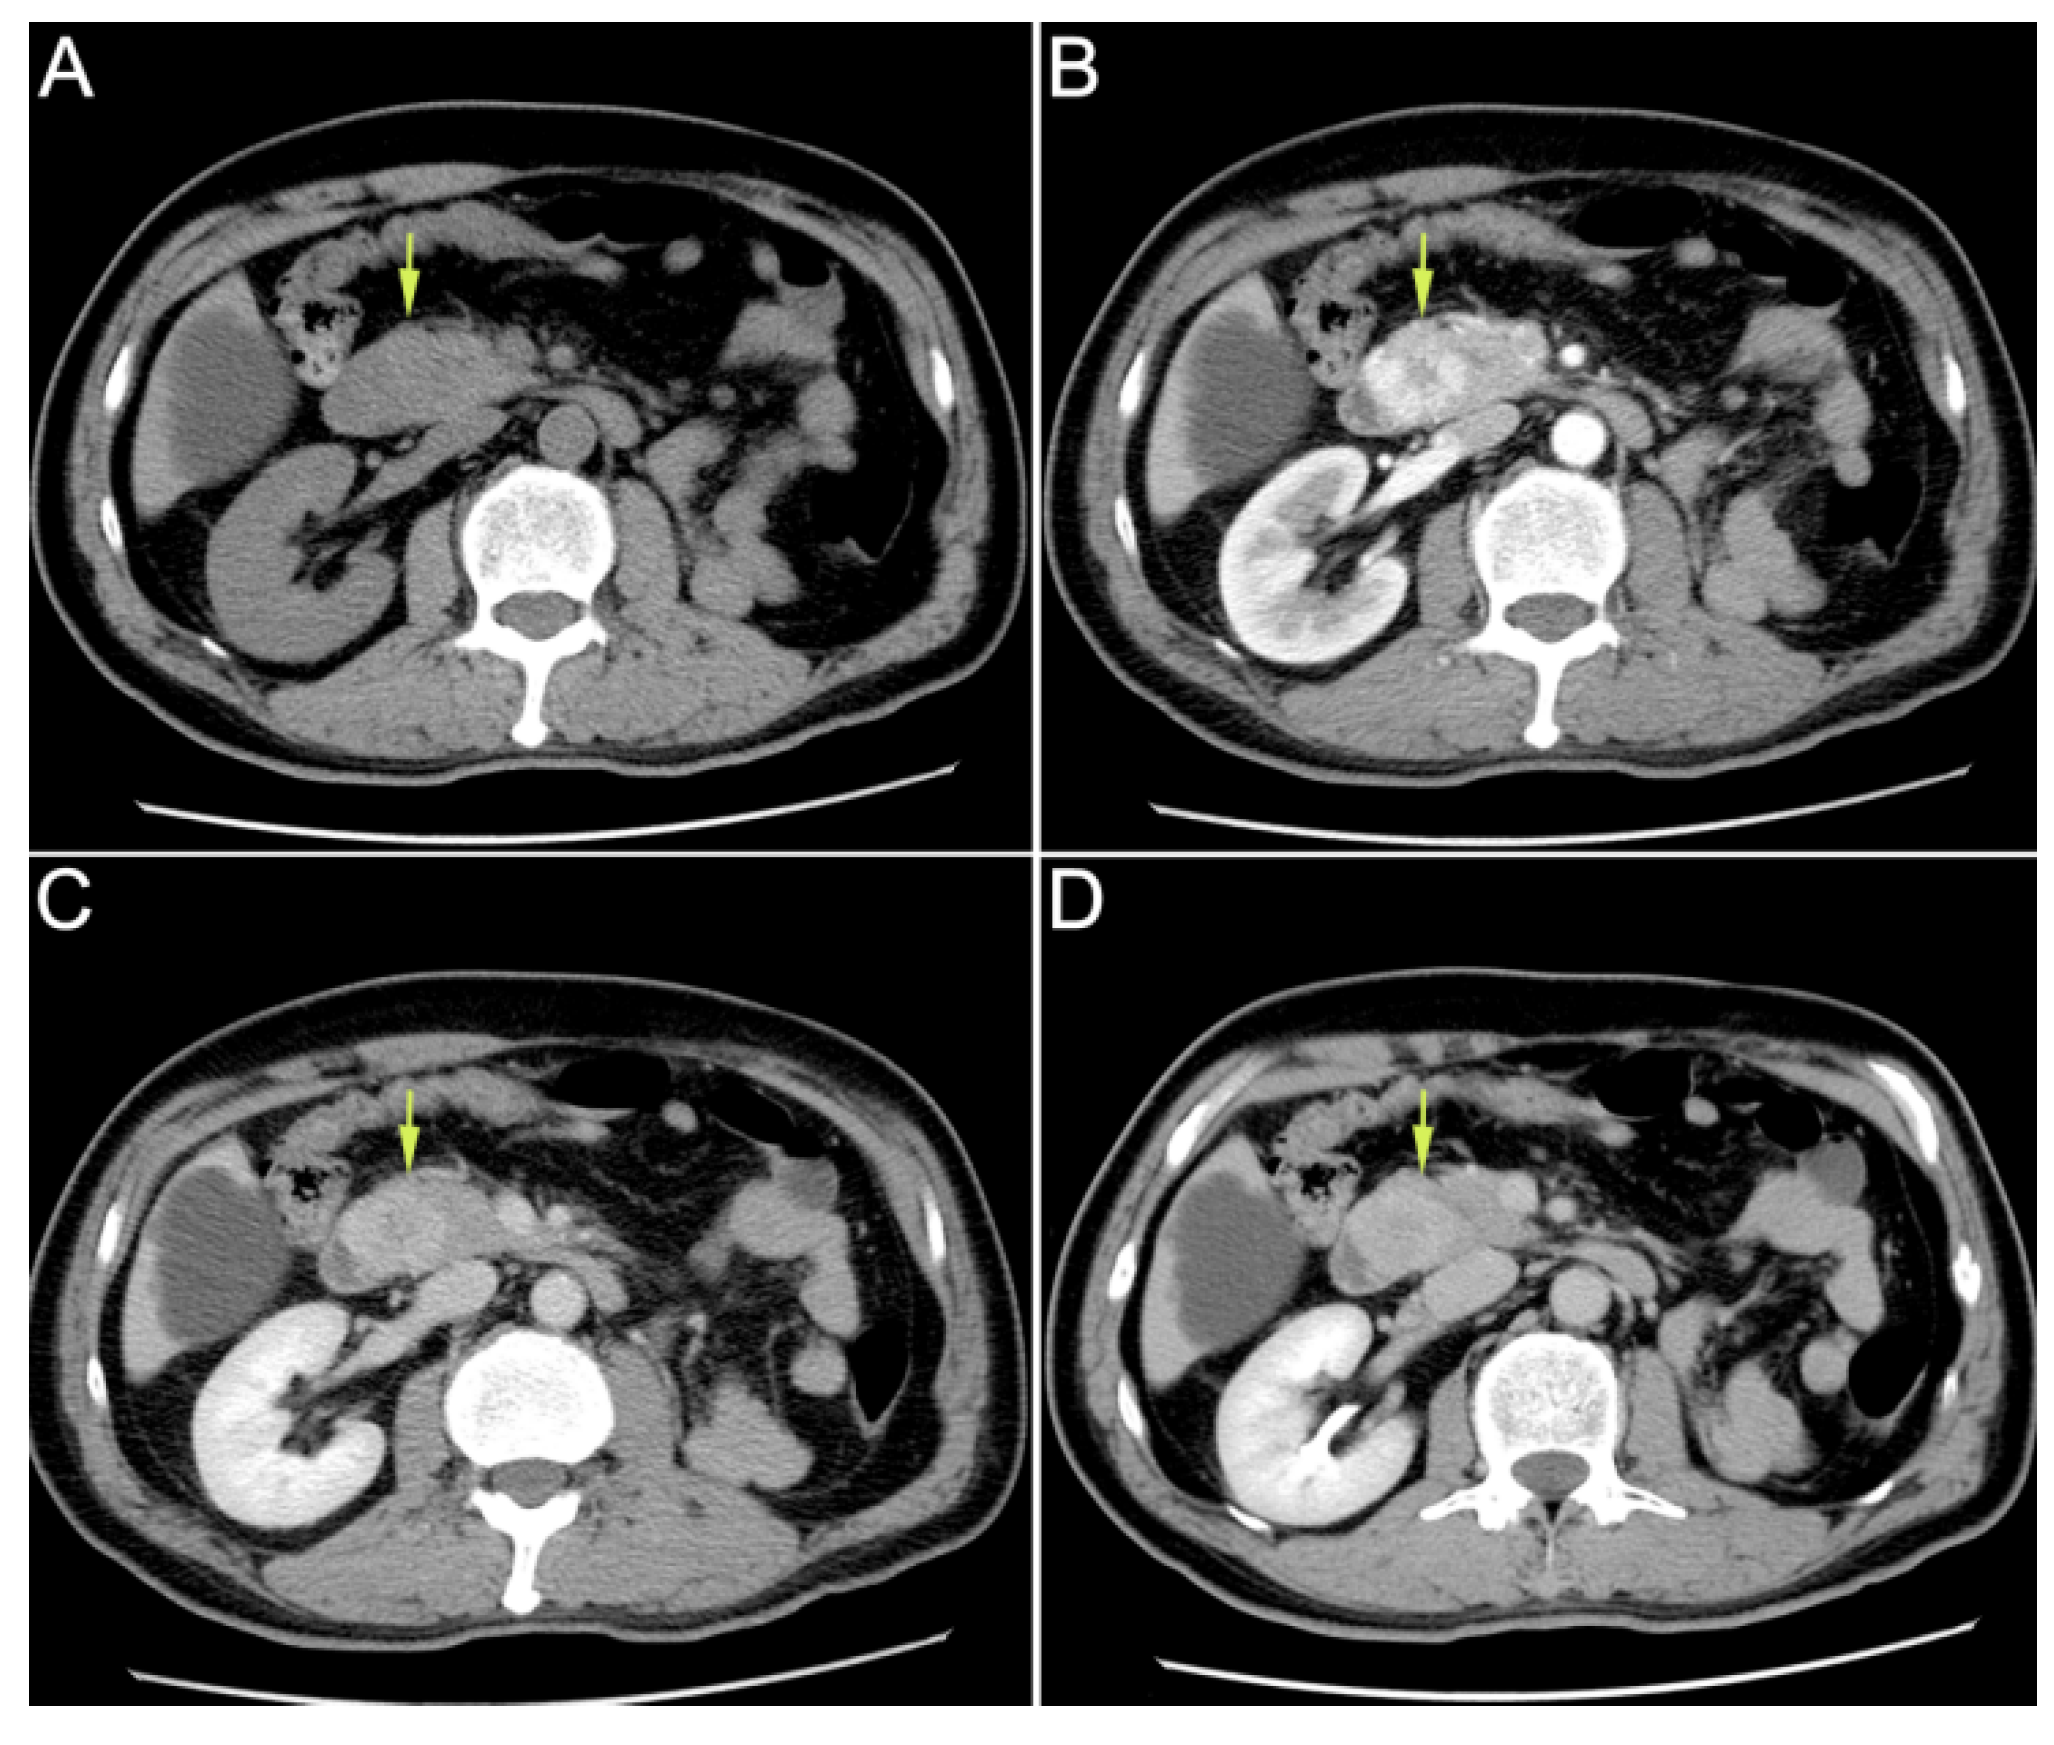

Enhanced upper abdominal computed tomography (CT) performed in the local hospital indicated ampullary mass. (A): plain scan phase; (B): arterial phase; (C): venous phase; (D): delayed phase. A 59-year-old male patient was hospitalized for “recurrent hematochezia for 8 days”. Enhanced upper abdominal computed tomography (CT), performed in the local hospital, indicated ampullary mass. On CT, the tumor showed uneven enhancement in the arterial phase, but the enhancement significantly weakened in the venous phase and delayed phase. Therefore, this imaging feature was significantly different from that in the primary ampullary tumor or pancreatic tumor. Duodenoscopy revealed duodenal papilla hemorrhage. Urinalysis showed no hematuria. After conservative treatment, the hemorrhage was not resolved. Then, the patient was transferred to our hospital for further treatment. He had received radical nephrectomy due to clear cell renal cell carcinoma (ccRCC) of the left kidney 16 years ago. The CT scan mentioned above revealed that his right kidney was normal. On admission, his laboratory tests results were as follows: leukocyte count of 3.9 × 109/L; neutrophilic granulocytes percentage of 75%; C-reactive protein of 1.6 mg/L; hemoglobin of 102 g/L; total bilirubin concentration of 12.6 μmol/L; alanine aminotransferase of 16 U/L; aspartate aminotransferase of 19 U/L.